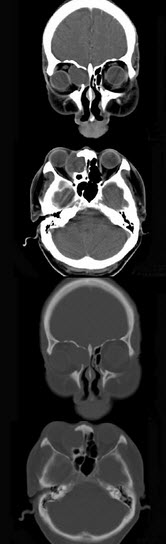

女性38岁,右侧眼球运动障碍伴眼球突出4个多月,CT扫描如图,请选择正确的描述和答案()

A、右侧筛窦内可见囊性肿块影,边缘光整

B、囊性肿块向右侧眼眶内突入,压迫内直肌

C、右侧眶内壁呈受压变薄、断裂

D、考虑为右侧筛窦黏液囊肿

E、考虑为筛窦癌

A,B,C,D